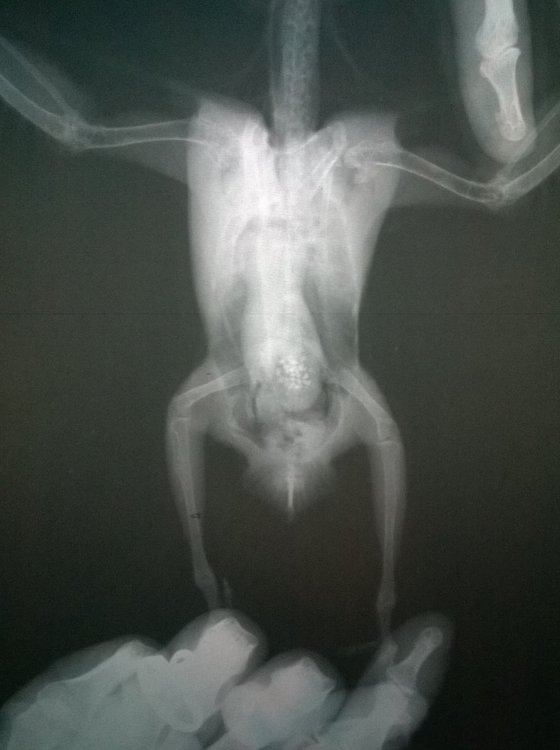

г.Новодвинск. Специалистов нет. Проблема: плохо ходит, падает, не ест. Помет изменился. Предположение: застревания яйца Попугай корелла самка 6 лет. Клеточное содержание. Практически без выпуска из-за собаки,детей.Неслась практически ежегодно. Корм только РИО для средних попугаев, не ограничено. Съедала много.Пила воды много. Овощи, зелень, мин.подкормка,сепии и т.п. в рационе отсутствовали. На окне в клетке в комнате. Проблемы начались в начале недели, после того как снесла яйцо. Упала с жердочки, и практически перестала ходить. Обратились к девушке волонтеру по птицам. Единственному человеку который хоть как то попытался помочь и отправил сюда. Рекомендовано: Рентген(сделан), анализы( бак.посев,копрограмма) НЕ ДЕЛАЮТ в гор.вет.лаб. Обратиться к специалисту(поэтому тут). Улучшить условия кормления и содержания(делаем). Помогите спасти птицу,пожалуйста.Ошибки осознали..исправим,но очень нужна помощь. Назначено: вазелиновое масло 0,4мл в клоаку, 0,1мл в клюв 1 раз в сутки. . Водяная баня. Кормление насильно через шприц запаренной крупой с яблочным пюре детским. Глюконат кальция ампульный по 0,05мл 1 раз в сутки, клюв. Мильгамма 1/8 таблетки в клюв. Энтеросгель 0,1мл в разведении 1:1 с водой. Нужна помощь в лечении(